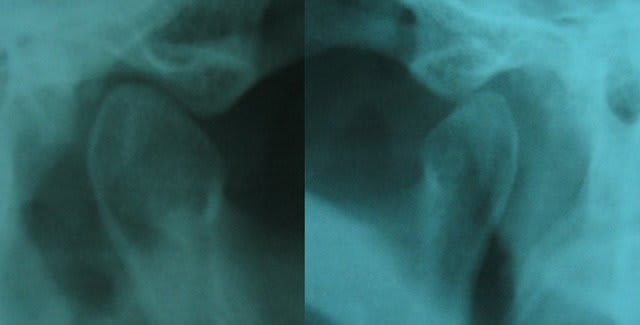

Tu nous montre les ATM, donc, c'est important pour toi. J'avoue ne pas y faire attention sur les pano. peut tu nous dire ce que cela t'apportes au niveau clinique ?

2/ Les ATM: effectivement y'a comme un décalage mais vu la localisation de la douleur (gonion) ça me parait pas prioritaire par rapport au traitement symptomatique sur 35 si elle est bien en cause.